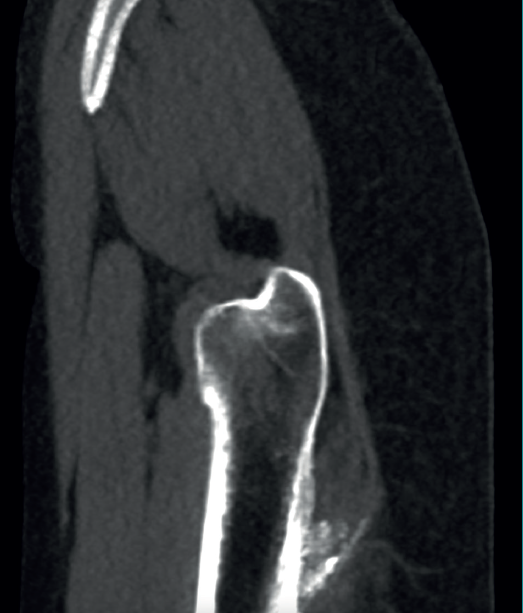

The physical examination revealed a limp-free gait and complete joint balance, with no positive signs of femoroacetabular impingement or inguinal pain. Muscle strength was preserved and similar to that of the contralateral side. She experienced intense pain on palpation of the insertion of the gluteus maximus, referred proximally to the ipsilateral buttock. The pain was reproduced on extension against resistance, and prevented sitting for long periods. Plain radiographic and computed tomography (CT) images revealed calcific tendinosis affecting the aponeurotic prolongation of the gluteus maximus in proximity to its insertion in the upper region of the linea aspera of the femur  (Figures 1 and 2) Magnetic resonance imaging (MRI) of the hip showed a labral tear, that proved asymptomatic in the physical examination. In view of the clinical picture of radicular pain, an MRI scan of the lumbar spine and subgluteal space was also performed, ruling out radicular involvement or sciatic neuritis. Her previous treatment over the three years of evolution of the disorder included oral nonsteroidal anti-inflammatory drugs, a specific physiotherapy programme and several ultrasound-guided corticosteroid injections with positive results - though a last session showed no response. Due to the severity and chronicity of the symptoms and their resistance to conservative treatment, surgery was decided to clean and remove the intratendon calcification endoscopically.

reacae.31181.fs2402007en-figure2.png

In cases of calcific tendinopathy of the gluteus maximus, calcifications in the femoral metaphysis can be seen on plain radiographs, though a normal image may also be seen. Therefore, CT and/or MRI scans are usually necessary for establishing the diagnosis, exhibiting an irregularity or cortical erosion at the insertion of the gluteus maximus in the gluteal tuberosity, located on the posterolateral surface of the femur, distal to the greater trochanter, accompanied by areas of tendon calcification, local inflammatory signs and, in some cases, partial intratendinous ruptures(17). Use can also be made of CT-guided single-photon emission computed tomography (SPECT-CT), which pinpoints the anatomical location and assesses the activity of the lesion, and is of interest in the differential diagnosis in oncological patients(18).